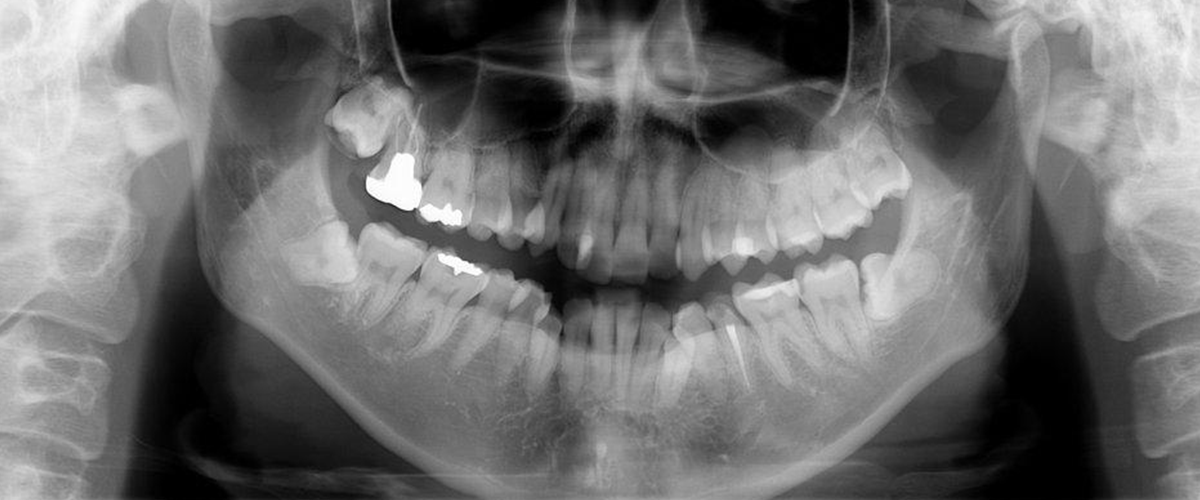

顎の骨は人により形態が異なり、その内部には数多くの神経や血管が通っています。通常のレントゲン写真では、骨の影になった神経や血管を確認することができません。

しかし、三次元の高画質画像を用いることで、断層方式パノラマX線写真や口内法X線撮影法では判別できない診断が可能です。

そのため、歯科用CTは、これらの神経や血管を傷つけてしまうような万が一の事故を未然に防ぐために欠かすことのできない装置です。

インプラントを埋入する部位の術前などに、骨の状態(質や厚み、高さ、形態など)を正確に診断し、的確な治療計画を立てることにより、より安全性の高い治療を行うことができます。